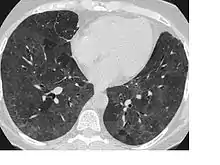

CT image showing diffuse GGOs throughout both lungs. An abscess is also noted in the right lung (screen left). - Adenocarcinoma in situ of the lung

Diffuse

The diffuse pattern typically refers to GGOs in multiple lobes of one or both lungs. Broadly, a diffuse pattern of GGO can be caused by displacement of air with fluid, inflammatory debris, or fibrosis. Cardiogenic pulmonary edema and ARDS are common causes of a fluid-filled lung. Diffuse alveolar hemorrhage is a rarer cause of diffuse GGO seen in some types of vasculitis, autoimmune conditions, and bleeding disorders.[6]

Inflammation and fibrosis can also cause diffuse GGOs. Pneumocystis pneumonia, an infection typically seen in immunocompromised (e.g. patients with AIDS) or immunosuppressed individuals, is a classic cause of diffuse GGOs. Many viral pneumonias and idiopathic interstitial pneumonias can also lead to a diffuse GGO pattern. Radiation pneumonitis, a side effect of pulmonary radiation therapy, can lead to pulmonary fibrosis and diffuse GGOs.[6]